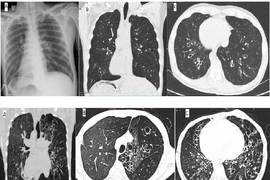

2 bệnh nhân mắc hội chứng Kartagener, đảo ngược phủ tạng hiếm gặp được phát hiện từ các triệu chứng viêm đường hô hấp tái diễn nhiều lần. Xét nghiệm gene hội chứng Kartagener thường khó thực hiện và tốn kém, chủ yếu dựa vào biểu hiện của tam chứng.

Hội chứng Kartagener là một rối loạn di truyền lặn trên nhiễm sắc thể thường hiếm gặp, gây khiếm khuyết trong hoạt động của lông mao ở phổi và nhiều cơ quan khác.